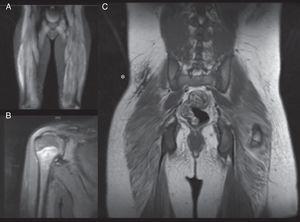

Los 5 casos presentaron debilidad muscular proximal, con elevación de una o más de las enzimas musculares (GOT, GPT, CK y aldolasa) y RMM en las extremidades superiores e inferiores con signos de miositis (fig. 1). En el electromiograma realizado en 4 pacientes se observó patrón miogénico en el bíceps y/o el cuádriceps. Dos pacientes mostraron ANA positivos a títulos bajos (1/160). En ningún caso se realizó biopsia muscular y en todos se realizó biopsia cutánea (tabla 1).

RMM de nuestros pacientes. A. Paciente 1. RMM-CE. Aumento de intensidad en secuencia STIR en región glútea y vasto lateral, indicativo de edema muscular, signo de inflamación muscular, que en el contexto del paciente confirma la miopatía. B. Paciente 4. RMM-hombro. Aumento de intensidad de la señal de deltoides derecho y fascia muscular, asociada a mínima cantidad de líquido en bursa subacromial. C. Paciente 5. RMM-CE tras instauración de tratamiento. Nótese la placa de calcinosis cutis en la región lumbar baja derecha (*) visualizada como una placa hipointensa.